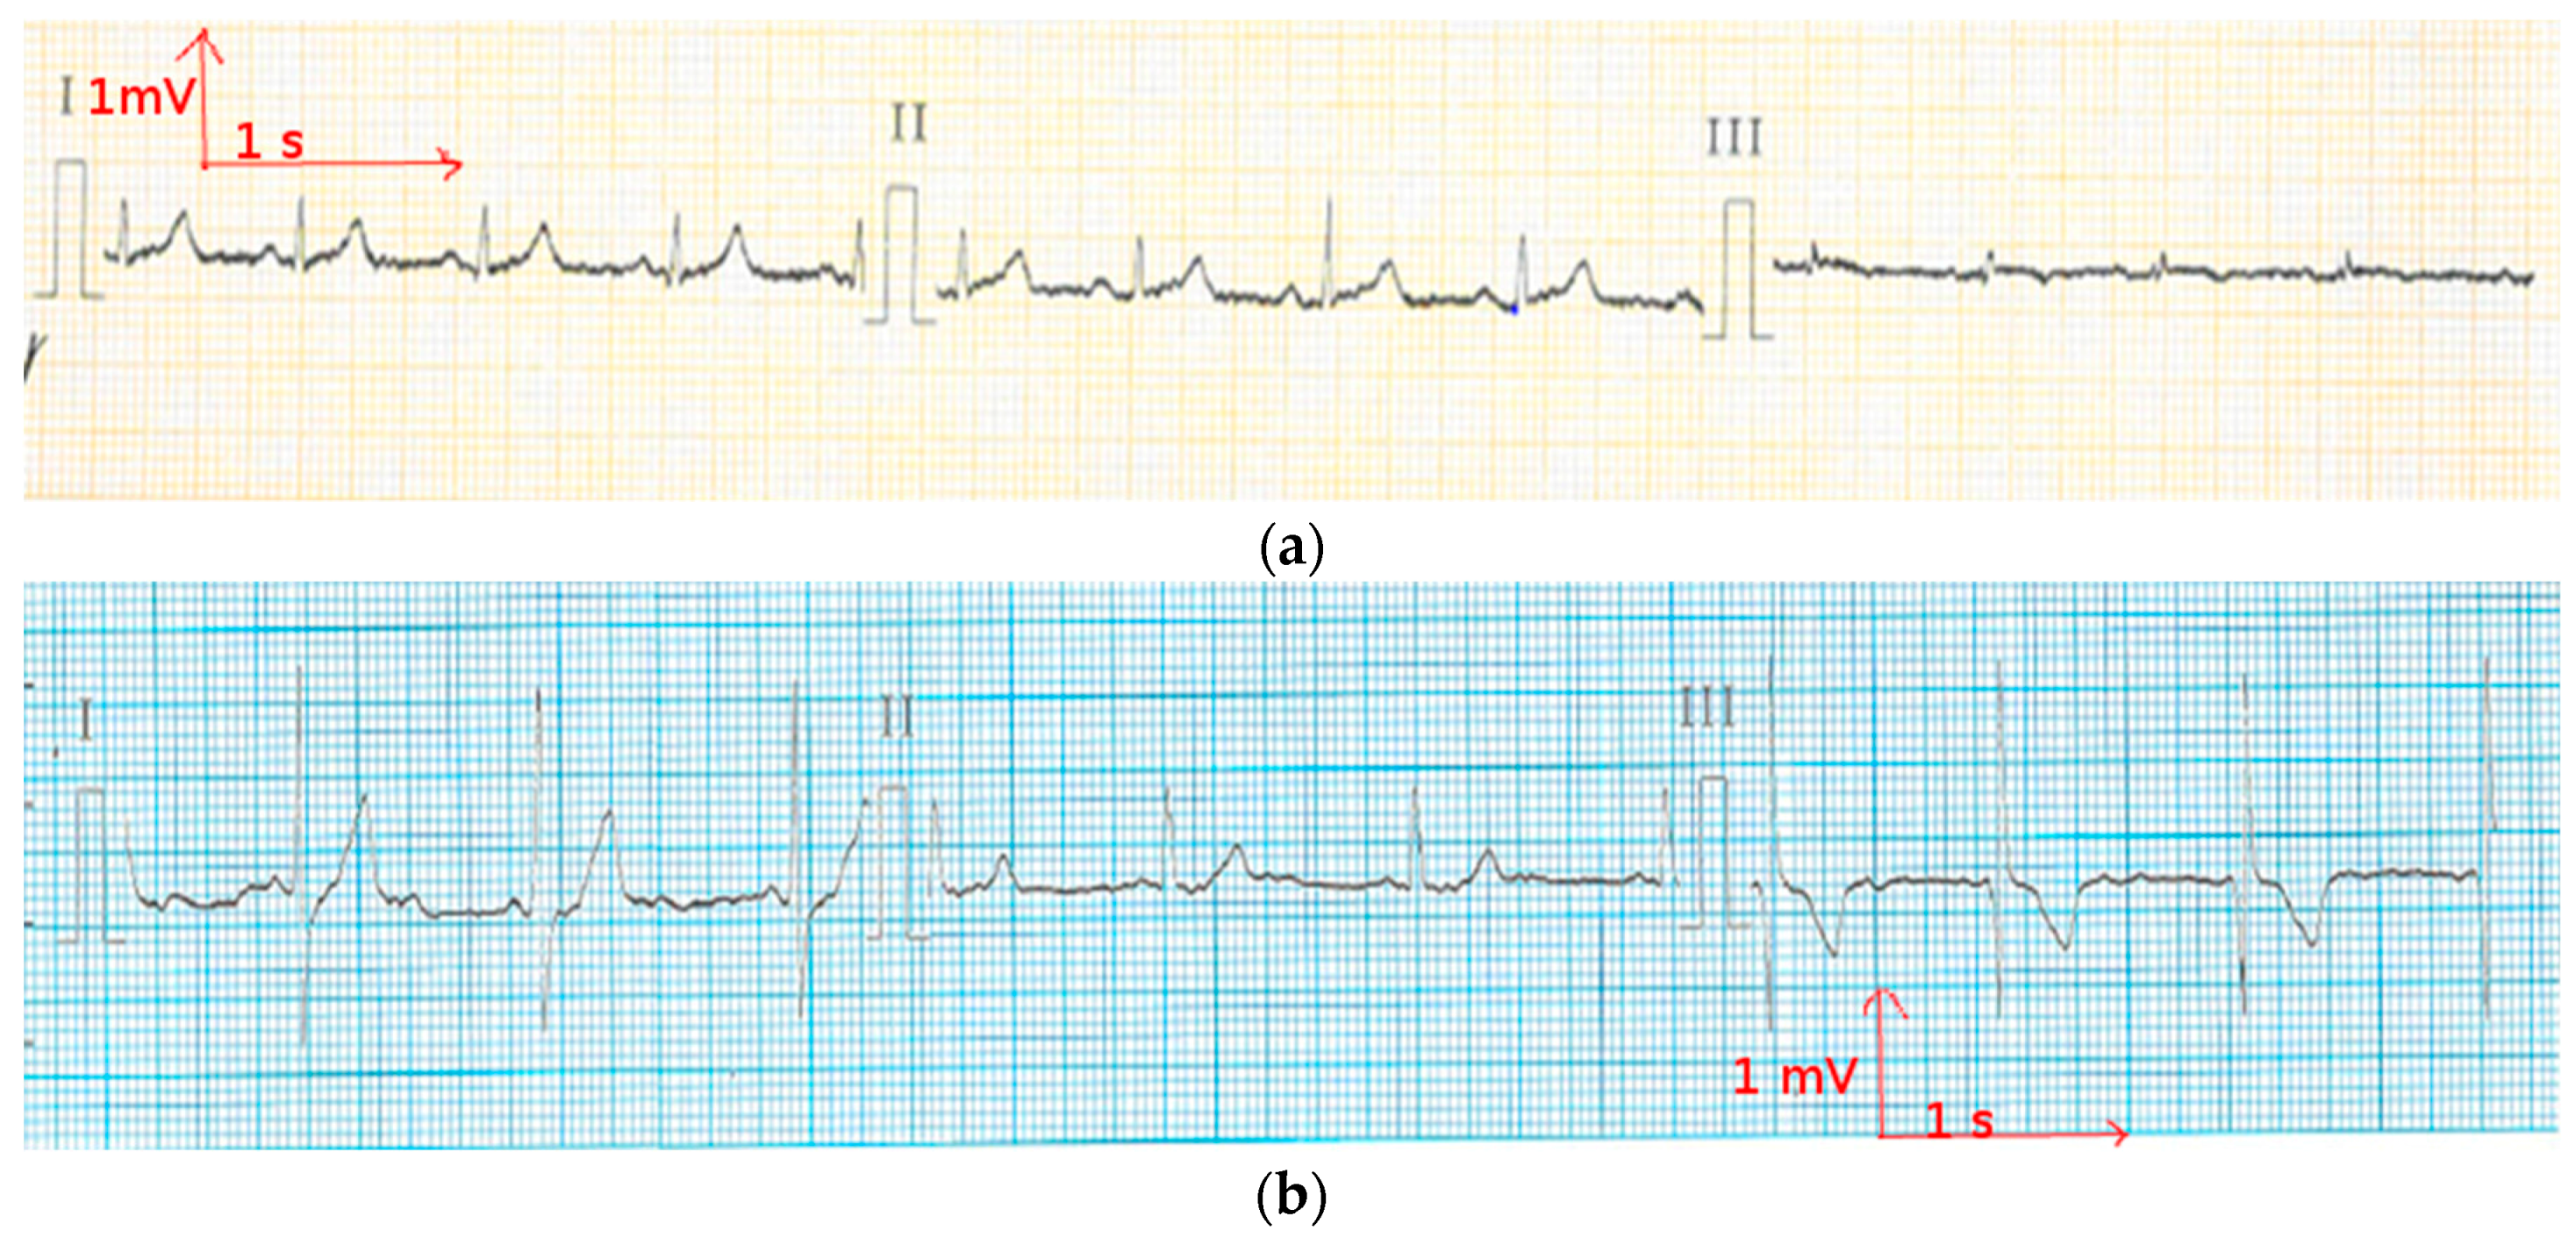

3.3. Evaluation of Textile Electrodes in ECG Monitoring